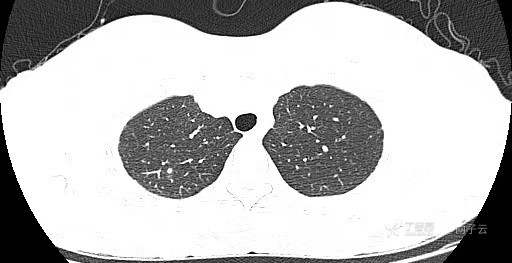

患者女,44岁,无特殊症状,做体检时发现右肺结节。查到1年前的体检CT片,右上肺当时就有一个直径约3mm的微小结节。两次检查检查图片如下:

以下三张为1年前CT片: